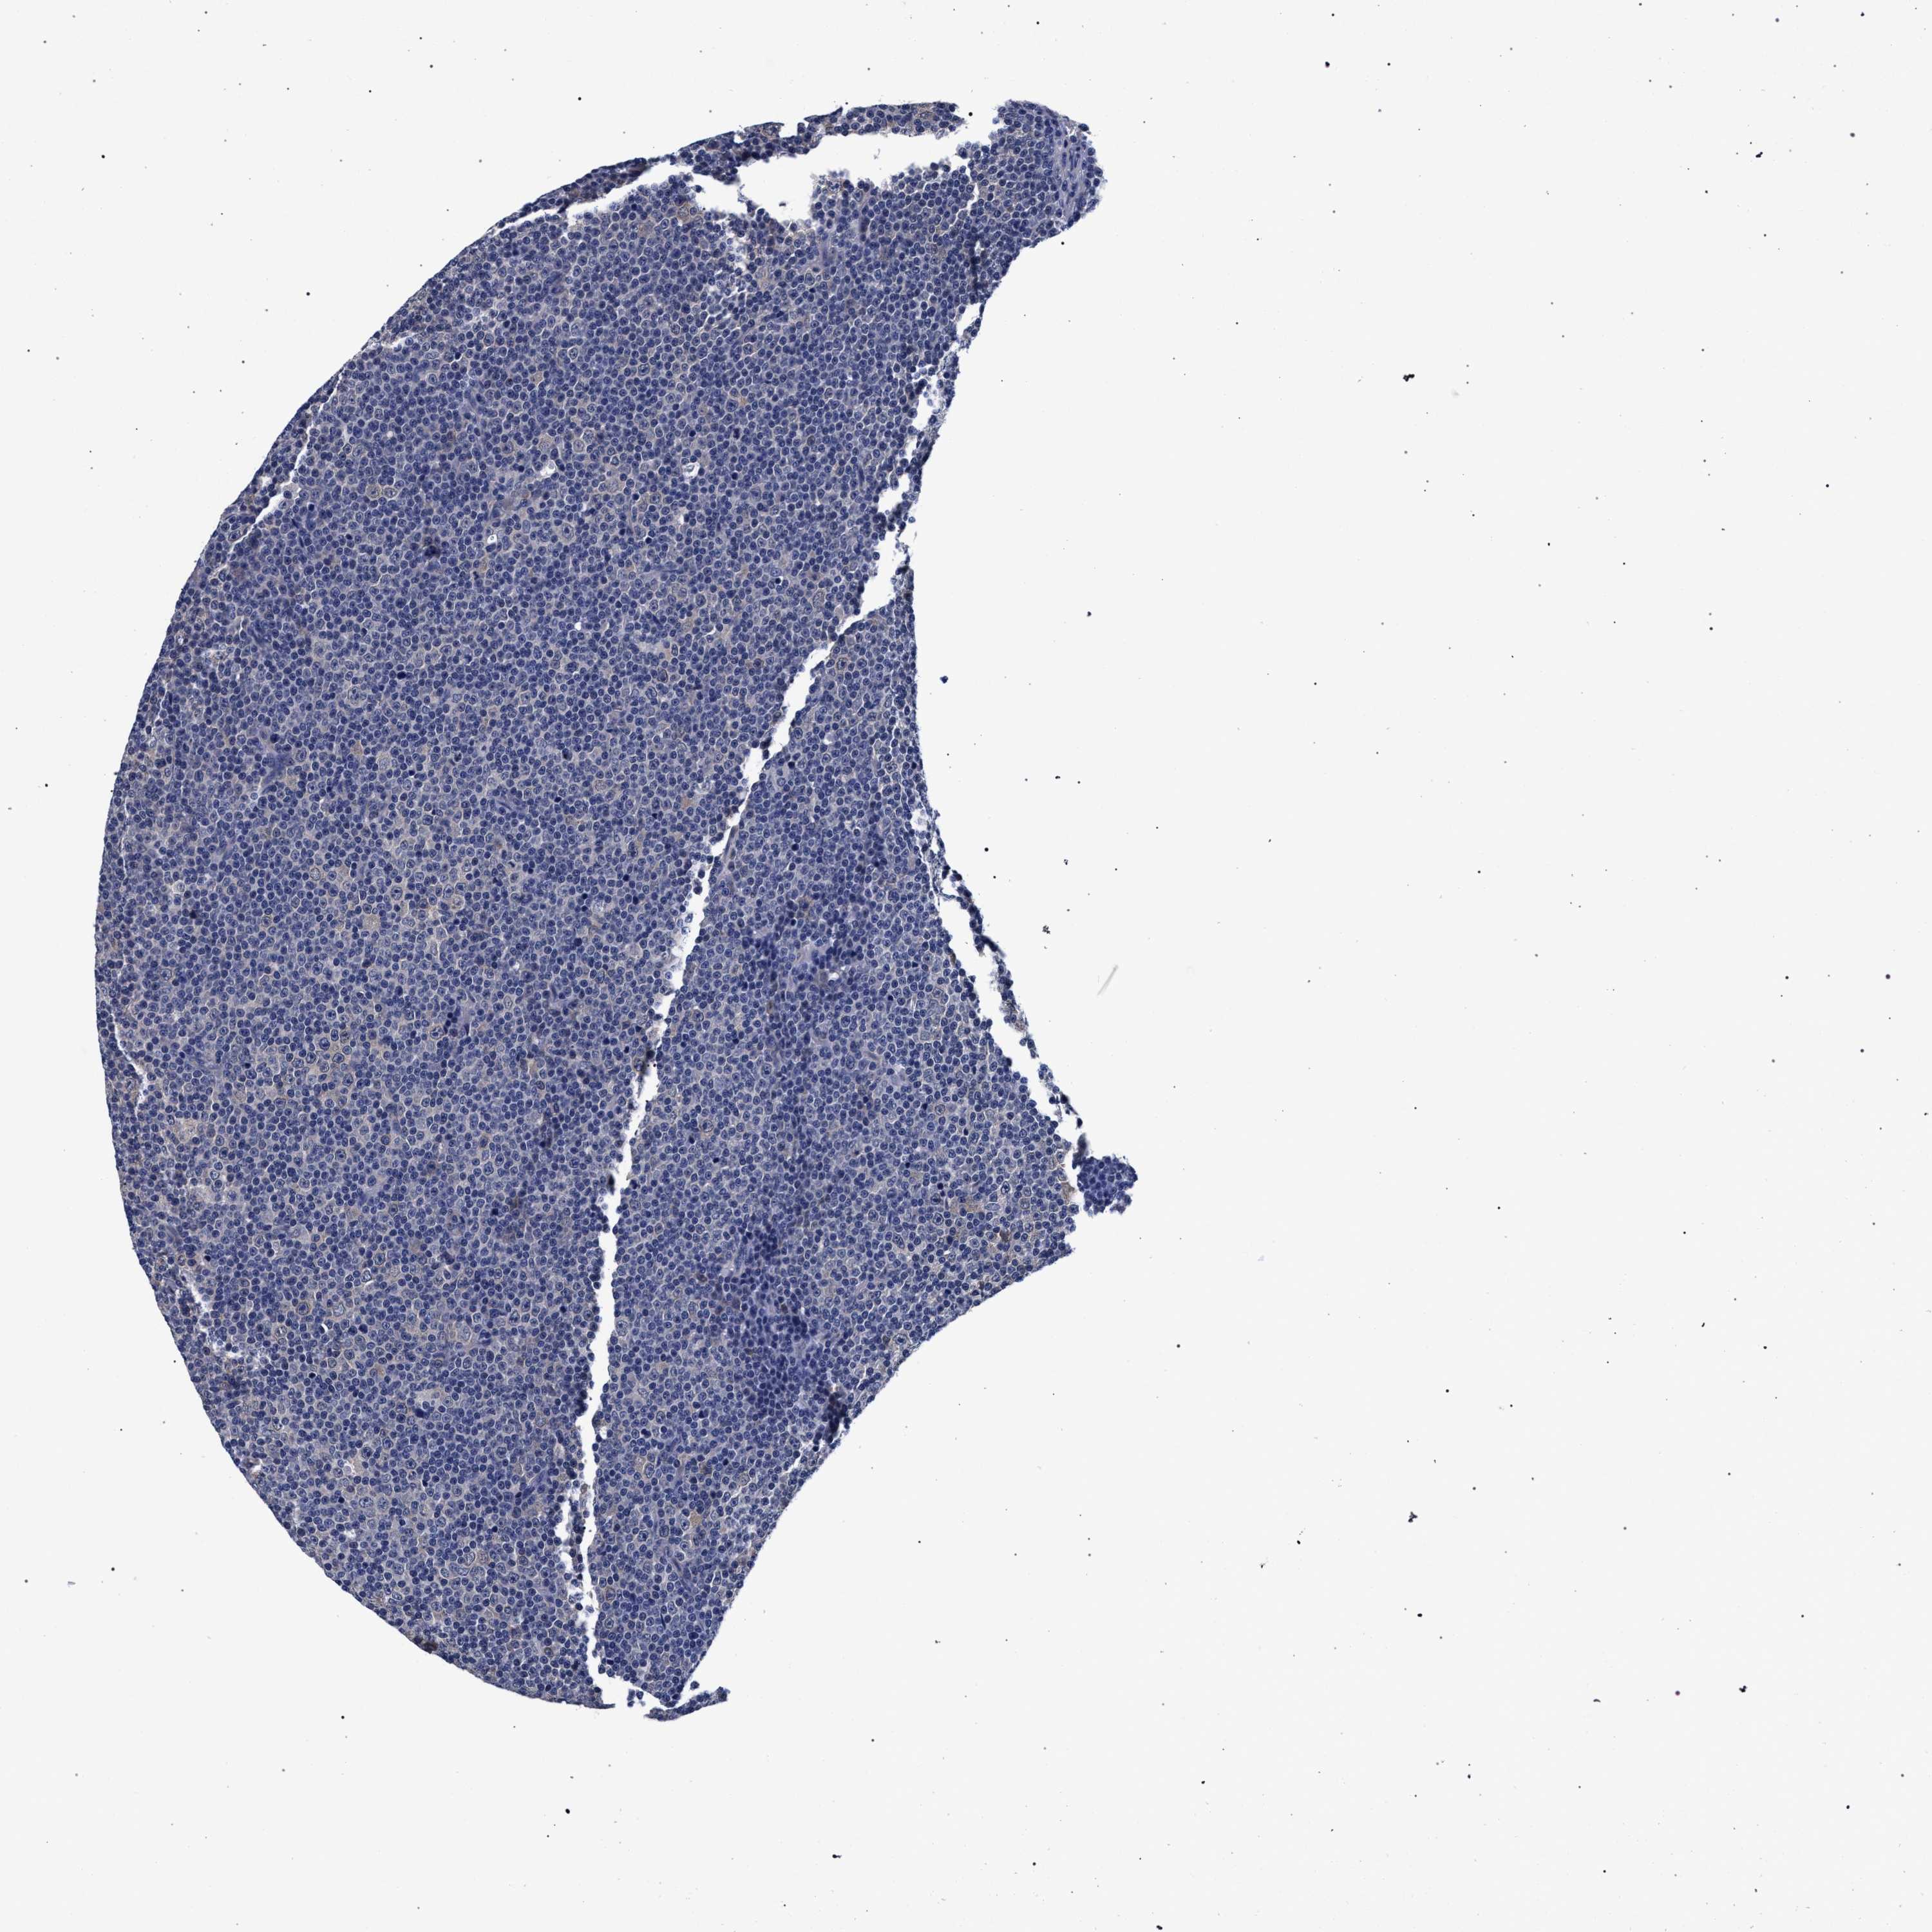

CANCER LYMPHOMA Show tissue menu

LYMPHOMA - Protein expressioni

A mouse-over function shows sample information and annotation data. Click on an image to view it in a full screen mode. Samples can be filtered based on level of antibody staining by selecting one or several of the following categories: high, medium, low and not detected. The assay and annotation is described here.

Each image is clickable and will lead to virtual microscopy that enables deeper exploration of all samples and also displays staining intensity scores, fraction scores and subcellular localization as well as patient and tissue information for each sample.

Antibody HPA021497

Hodgkin's disease, NOS

Malignant lymphoma, non-Hodgkin's type, High grade

Malignant lymphoma, non-Hodgkin's type, Low grade